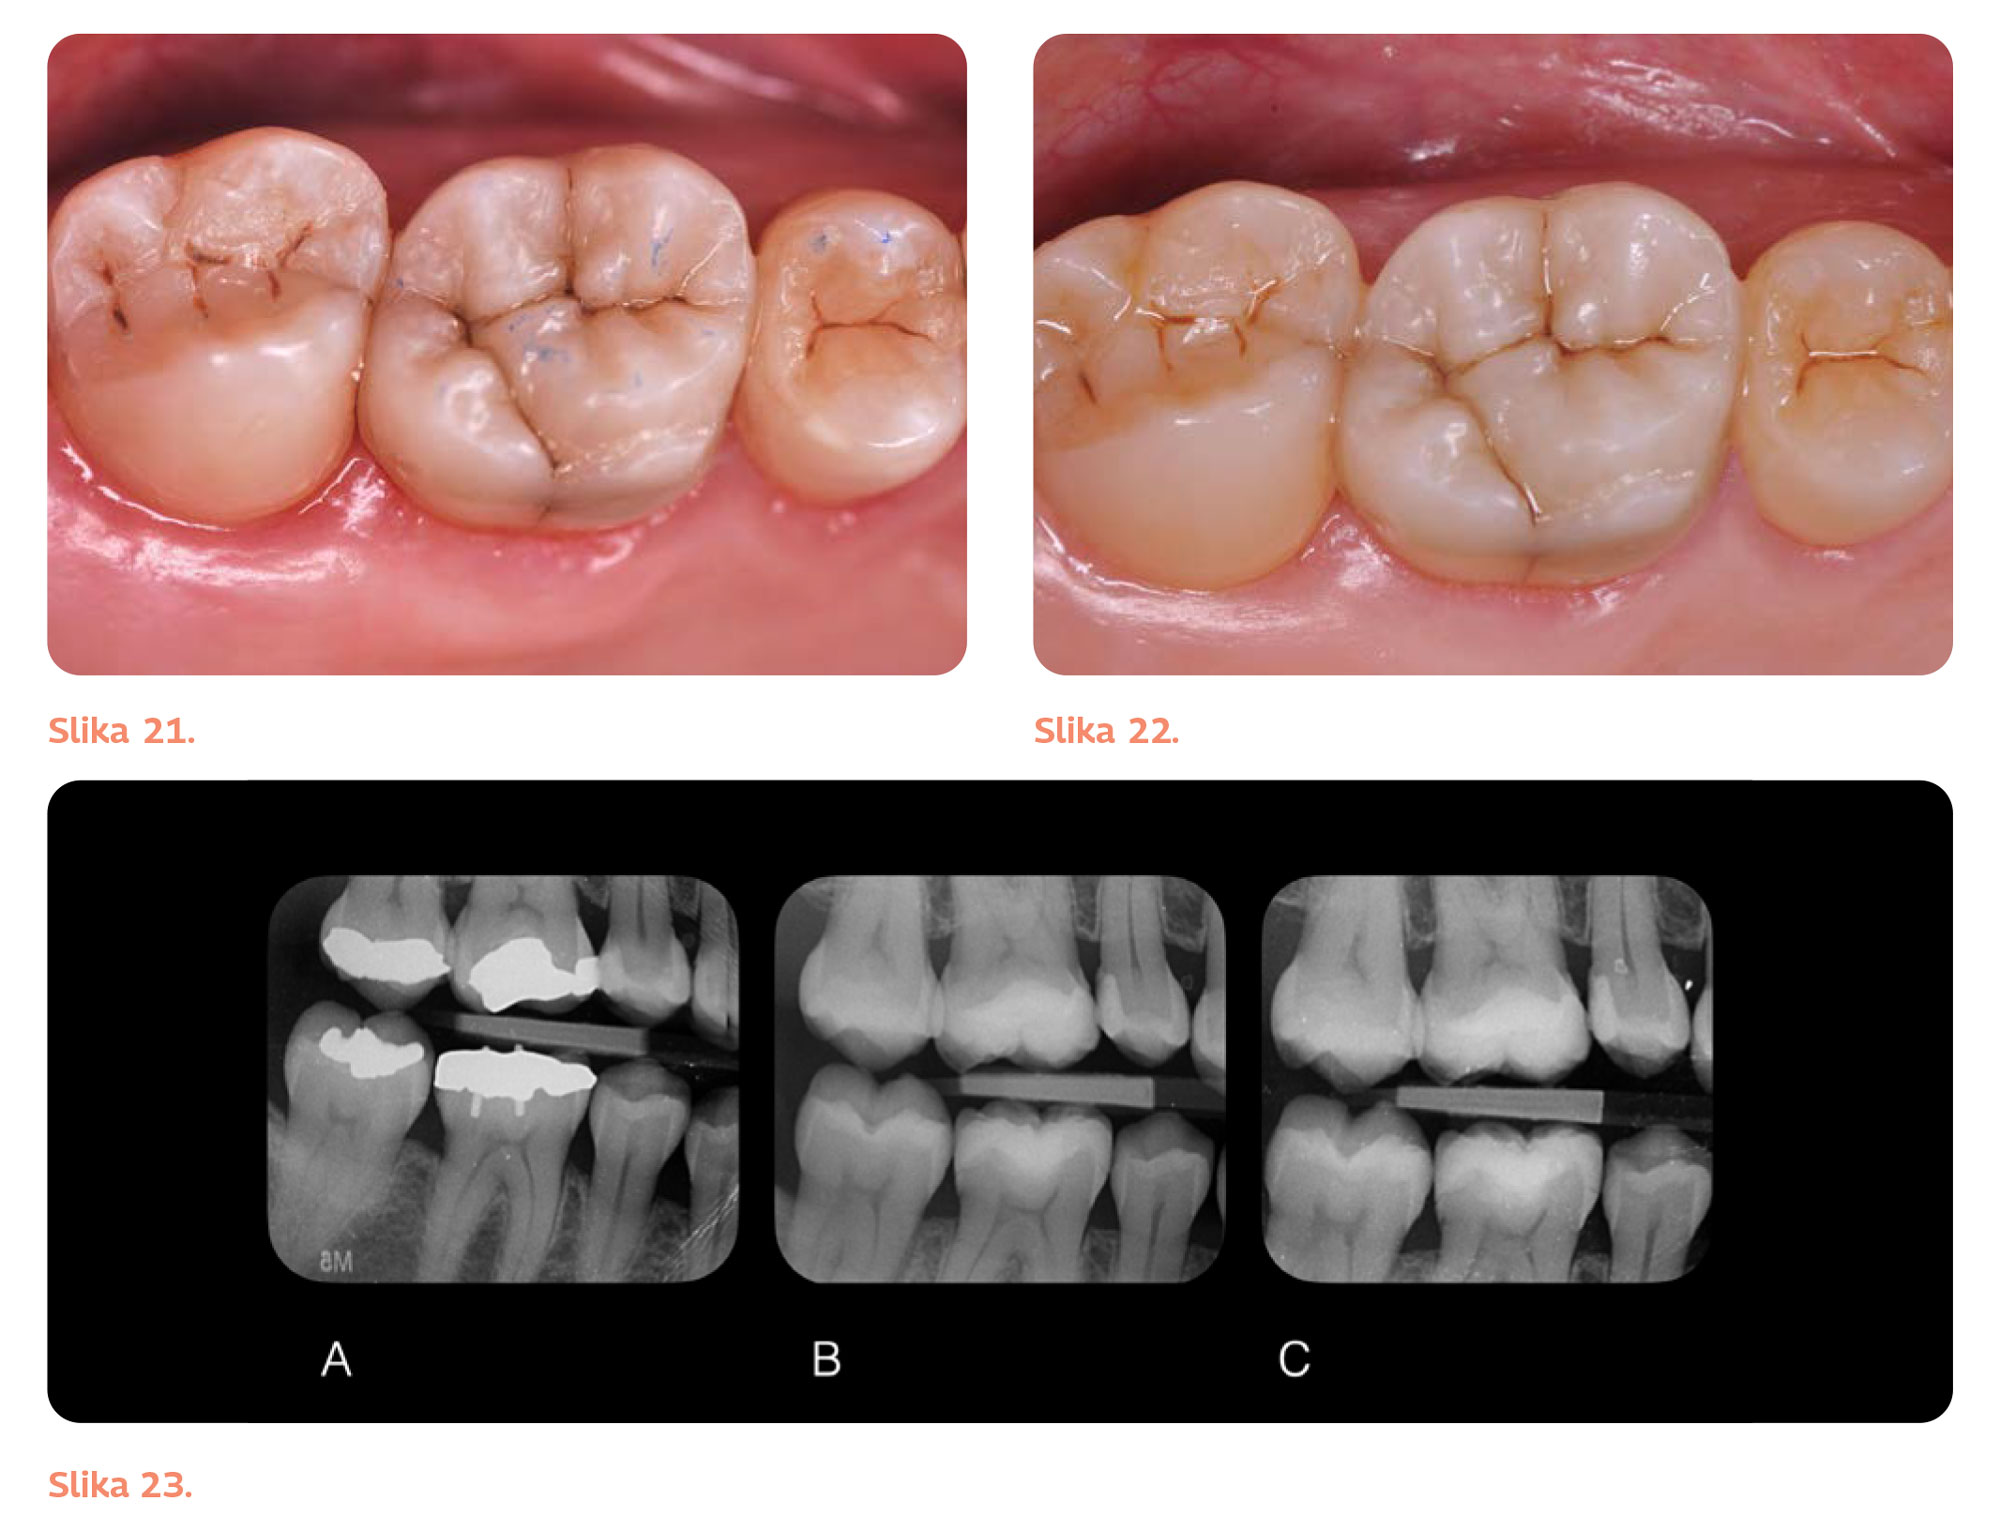

Slika 21. Izvršene su okluzalne korekcije radi postizanja funkcionalnog i estetskog rezultata.

Slika 22. Finalni rezultat godinu dana nakon restaurativnog tretmana.

Slika 23. Radiografski snimci pre (A), nakon tretmana (B) i godinu dana nakon tretmana (C).